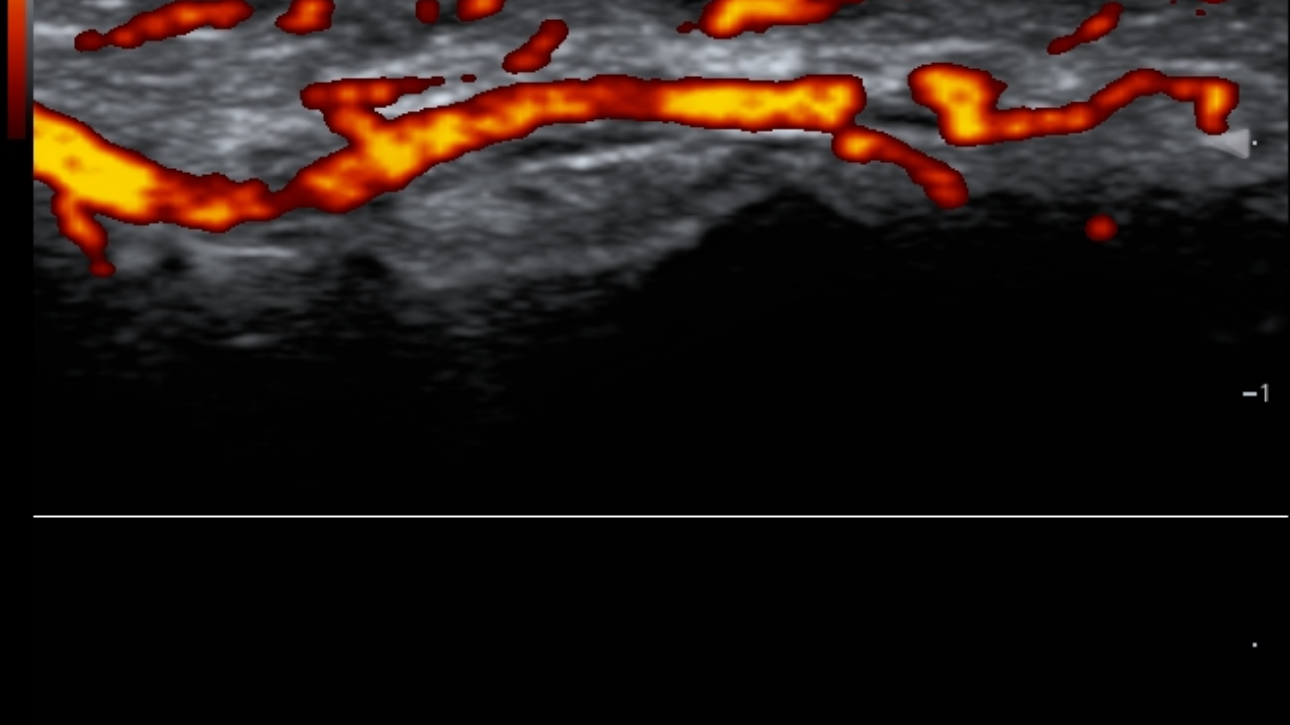

Based on smart track of vessels, it can automatically optimize Color/Power and PW spectrum to reduce repetitive, time-consuming steps and simplify the vascular exam workflow:

- Real-time and automatically optimize Color box position & angle

- Real-time and automatically optimize PW sample volume position & angle & size